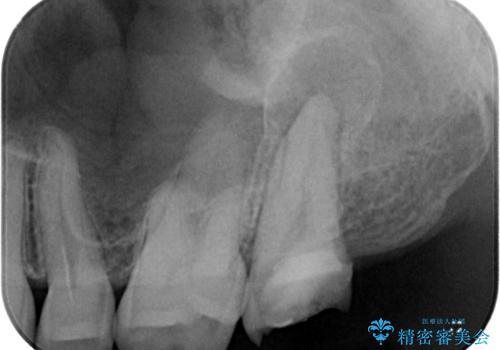

- 他院で虫歯治療の途中の歯を治療したいとのことで来院された患者様です。来院時特に症状もなく、根管治療途中の状態でした。レントゲン上でも大きい病変を認めました。治療方針として再度根管治療を行うか、抜歯をしてインプラントにする二つの方法をご提案しました。

根尖病巣も大きかったため先に抜歯を行い、1ヶ月後にインプラントを埋入しました。